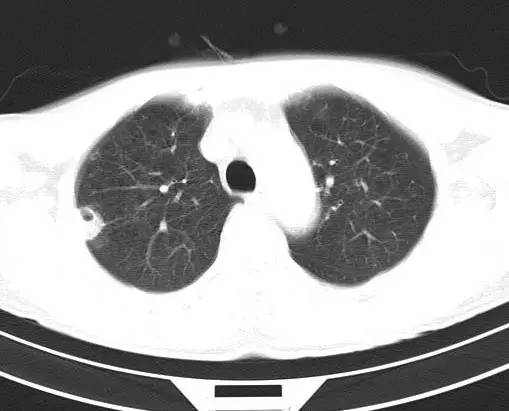

治疗前CT(图1-8):两肺胸膜下散在多发斑片状、结节状伴空洞影,边缘欠清晰。